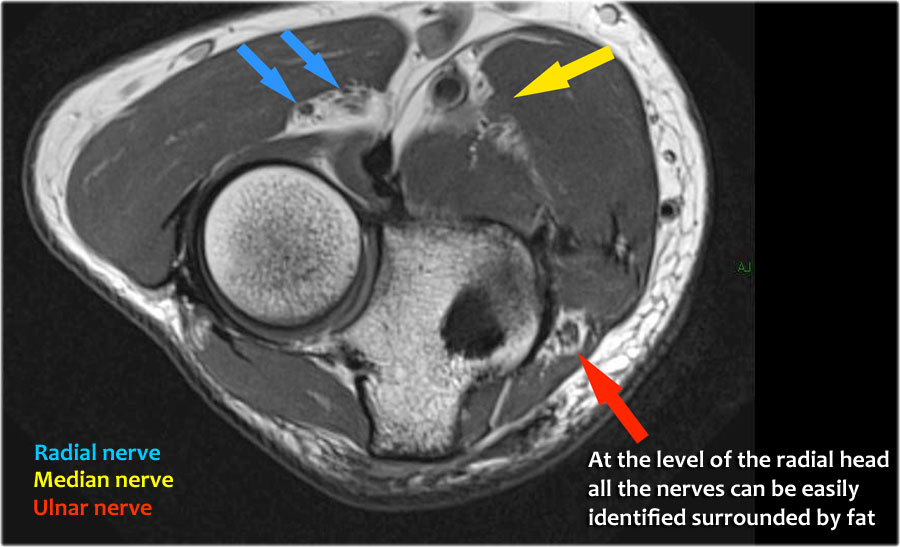

Dây thần kinh quay có thể được xác định rõ nhất ở mức chỏm xương quay, nơi có thể quan sát thấy các nhánh nông và nhánh sâu trong ống xương quay (mũi tên).

This is a very consistent place to find the radial nerve.